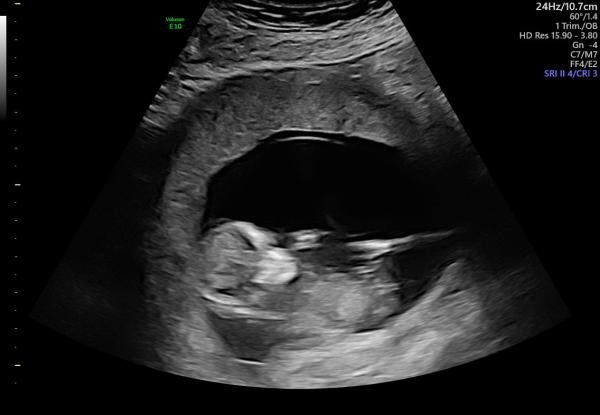

Rul avklarat och jag kan äntligen slappna av lite! Magkänslan hade rätt och förra ultraljudet fel, det blir en liten flicka och jag blev framflyttad till 7/12 så redan vecka 20 nu :D

Jag gjorde ju mitt med nu den 14e, känns så skönt att få se de där bebisarna större och se ut som små barn nu!! :D fick reda på att min moderkaka slutar precis vid öppning med så ska tillbaka när jag är i vecka 32 igen för ultraljud. Hoppas moderkakan flyttat på sig som den ska :)

Kub idag! Hjärtat slog och fick låg risk. Höll andan ända fram tills att hon sa att hjärtat slog. Nu ser klumpen mer ut som en bebis <3